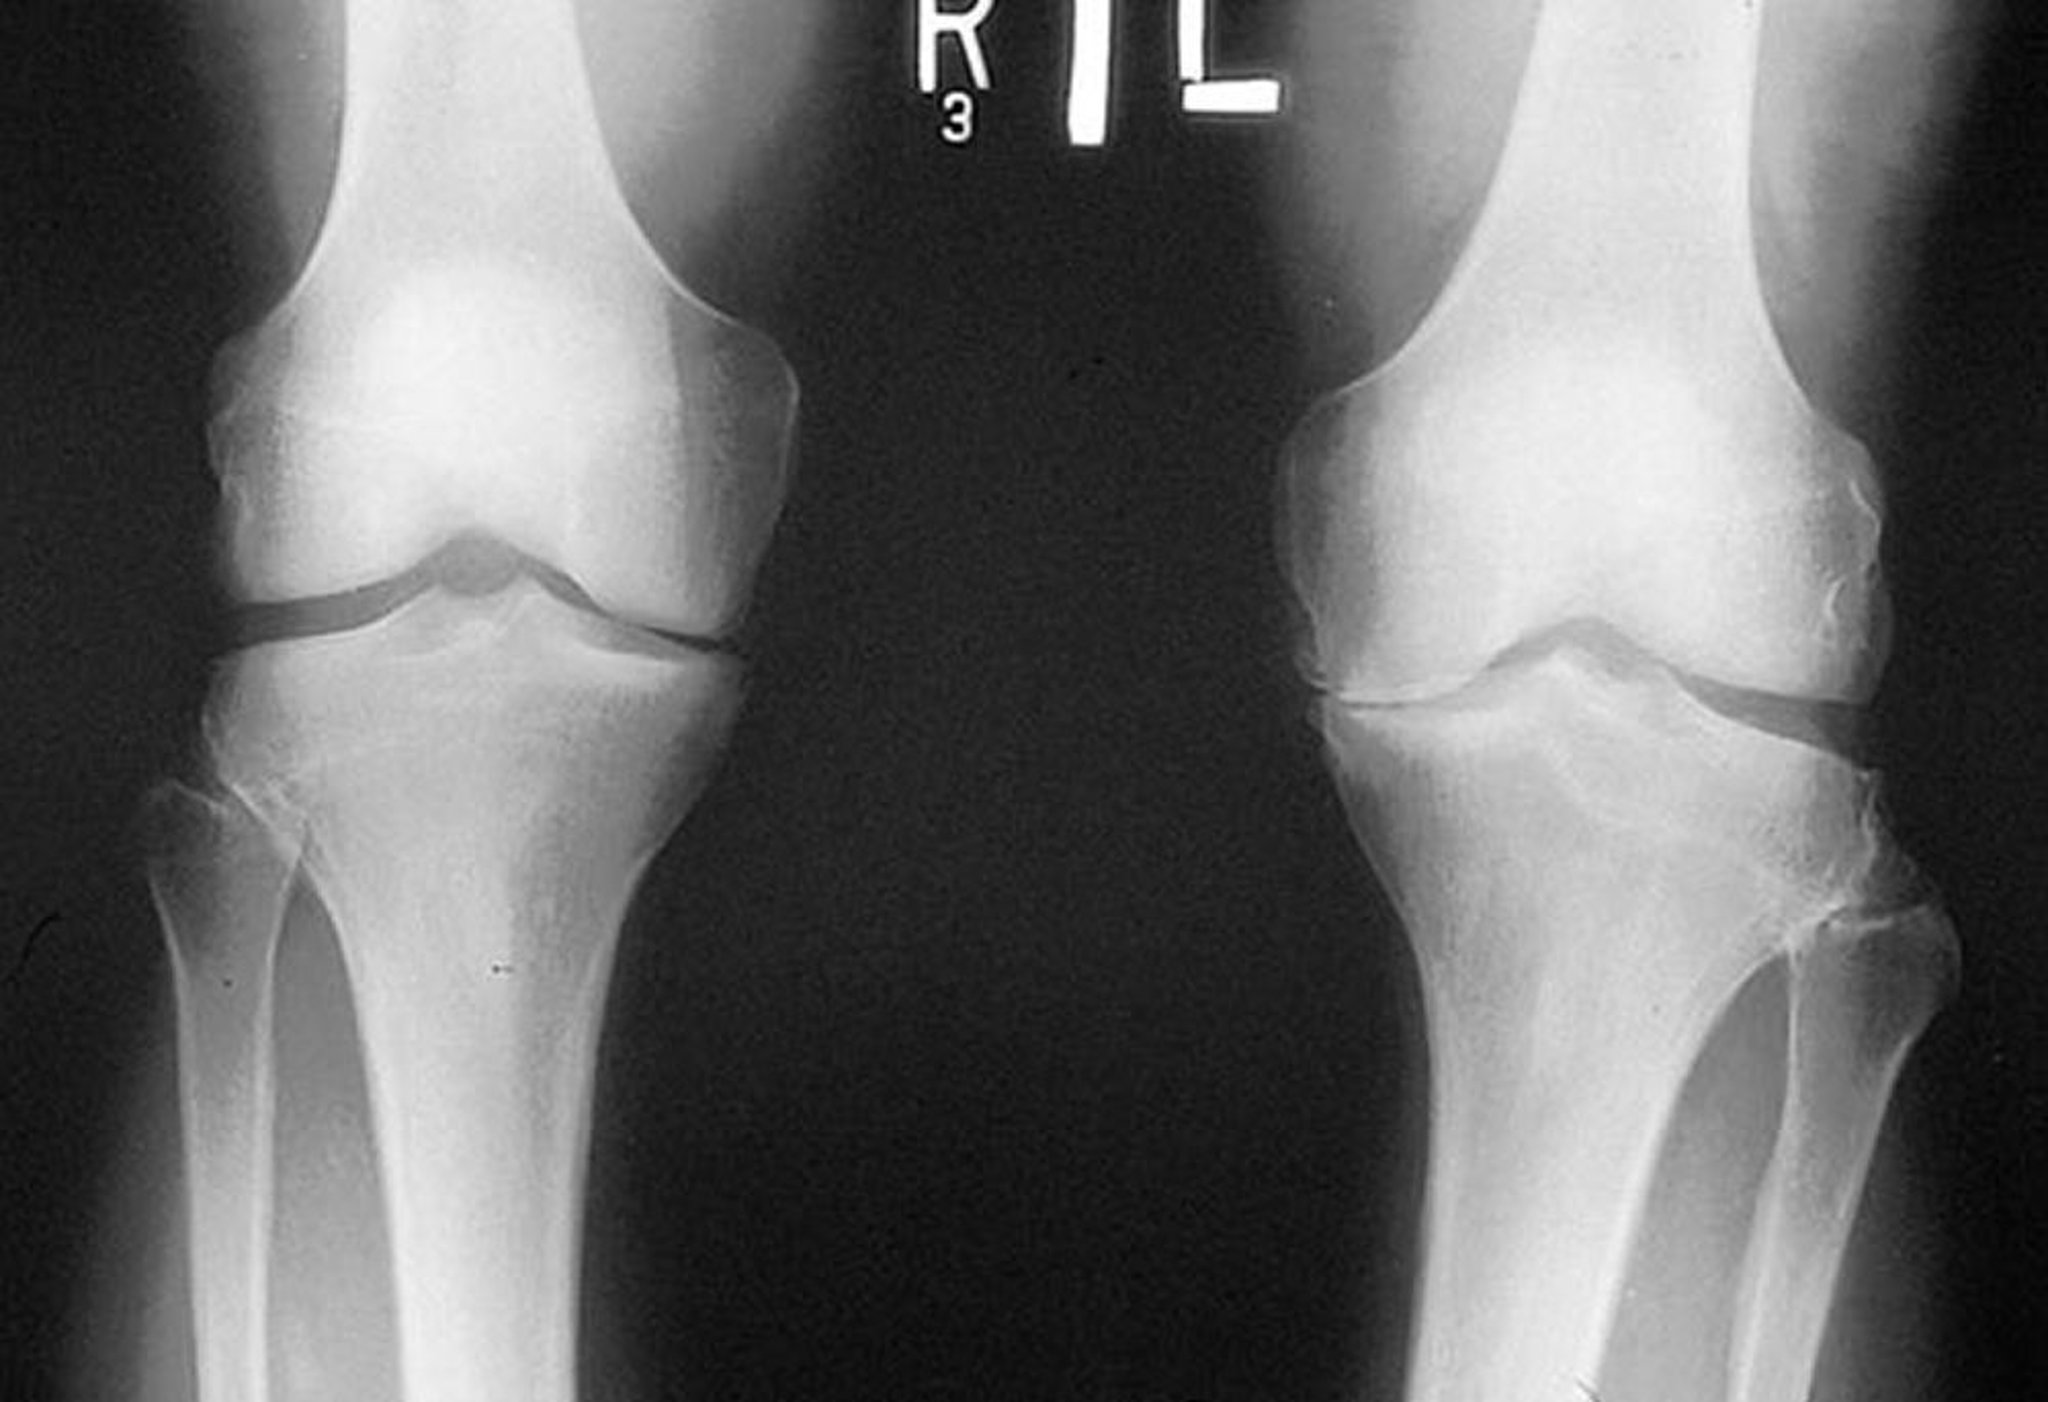

Radiografia do joelho na osteoartrite

Radiografia feita enquanto o paciente está em pé mostra que o espaço de articulação tibiofemoral no compartimento medial de ambos os joelhos é estreito, particularmente do lado esquerdo. Os osteófitos marginais são visíveis. Há desgaste do platô tibial medial esquerdo.

By permission of the publisher. From Myers S: Atlas of Rheumatology. Edited by G Hunder. Philadelphia, Current Medicine, 2005.